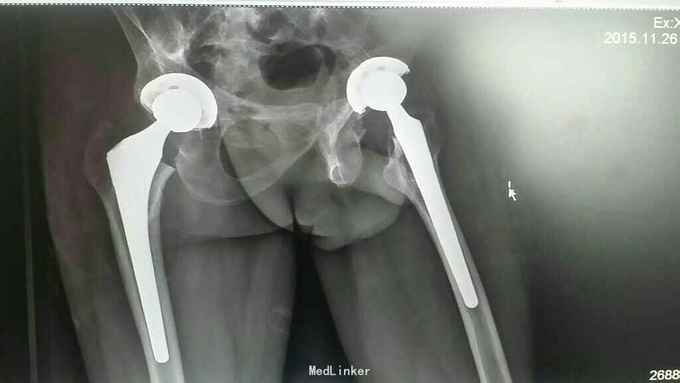

强制性脊柱炎是血清反应阴性的脊柱关节病,主要累及脊柱,关节和骨盆。长期患者因脊柱关节及脊柱上肌腱附着点的炎症导致慢性疼痛和僵硬,从而引起进行性强直。值得注意的一点是强直性脊柱炎患者HLA-B27阳性率达百分之九十以上,但是HLA-B27阳性者只有百分之五为强直性脊柱炎,所以,不能单纯依靠腰痛和B27阳性就诊断为强直性脊柱炎,结合影像和临床体征非常必要。很多强直性脊柱炎都是髋部疼痛,患者主诉腰痛患者臀部疼痛,很多交替性疼痛,症状不特异,夜间翻身困难,活动期夜间低热和虹膜炎病史见于很多患者,注意排查。很多症状类似于髋关节炎,偶尔会进展为双髋关节自发性融合,本例患者就是这样。患者诊断明确,完善术前准备后,患者腰椎后凸畸形不明显,本次手术科室讨论后决定,暂不截骨矫形治疗。采用髋关节前外及外侧联合切口有效地松解关节前方挛缩的软组织,矫正髋关节屈曲畸形,手术中见髋关节软骨面被破坏、消失,形成骨性强直。很难分辨股骨头与髋臼的真正界限,术中要尽量去除髋臼软骨面,保留软骨下骨。首选疼痛明显,畸形严重,负重能力差的一侧施术。因患者髋关节长期强直,周围肌肉挛缩明显,术后必须配合康复锻炼才能达到满意效果。

患者术后经过正规康复锻炼,髋关节疼痛症状消失,双髋关节屈伸活动范围达80度,髋关节屈曲畸形得到矫正,术后生活可以自理,可以处理正常家务劳动。 我们常规后外侧入路行髋关节置换手术,各位老师们不知有无选择此切口实行强直性髋关节置换?有什么更好的经验可以留言,谢谢!